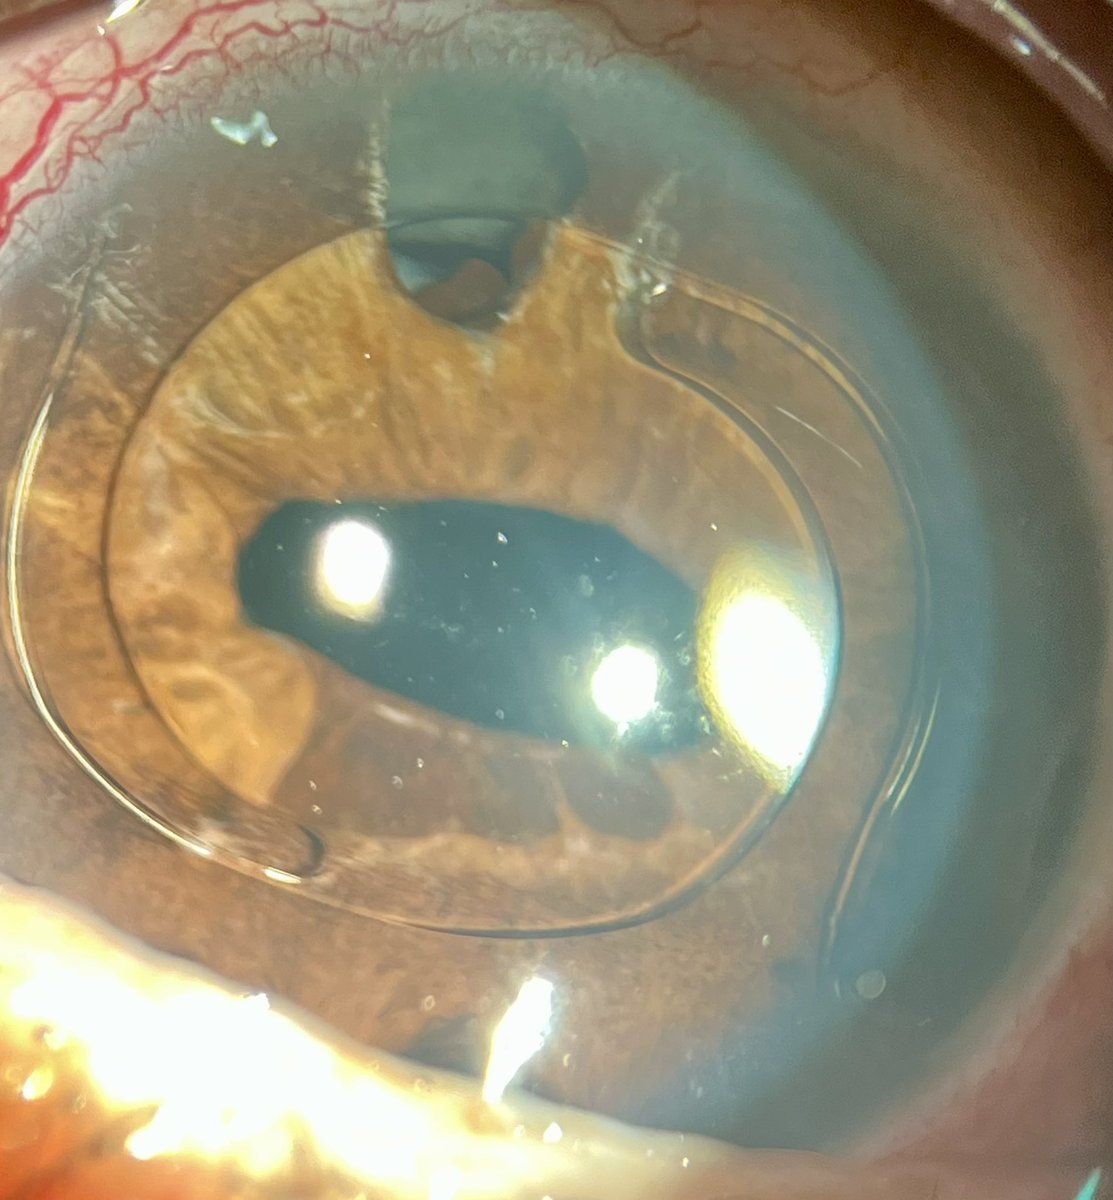

Eye MD | Fixing Eyes in Kashmir ❤️ | Cataract & Retina

🔗 Take the quiz: forms.gle/9DnrCQszG2BzhC… 📢 Clinical Ophthalmology MCQ Self-Assessment now live with answers & explanations across all subspecialties. Designed for postgraduates & residents preparing for IMM/Final fellowship exams. Mazhry-The Poet Ophthalmologist -ماہرِ چشم سخنور Acuity Eye Centre- The care your eyes need! Dr Hammad Nasti